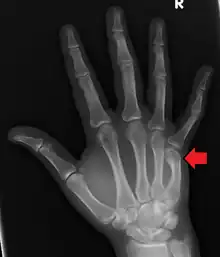

Boxer's fracture of the 5th metacarpal head from punching a wall

Classically, it occurs after a person hits an object with a closed fist.[2] The knuckle is then bent towards the palm of the hand.[4] Diagnosis is generally suspected based on symptoms and confirmed with X-rays.[4]

Diagnosis by a doctor’s examination is the most common, often confirmed by x-rays. X-ray is used to display the fracture and the angulations of the fracture. A CT scan may be done in very rare cases to provide a more detailed picture.[8]